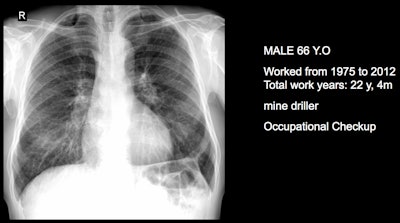

Three clinical cases courtesy of Luis Antonio Campos Calderon, MD.

The International Labor Organization (ILO) International Classification of Radiographs of Pneumoconioses is used for epidemiological studies, screening, and surveillance of workers exposed to dust in the workplace, and clinical purposes, and the National Institute for Occupational Safety and Health (NIOSH) B Reader Program certifies physicians in the ILO classification system. Each case should discuss its ILO classification and brief comments about the workflow, Campos Calderon noted.

The main diagnostic criteria are: Work history (minimum 10 years exposure to silica dust or other particles); chest x-ray (micronodular pulmonary fibrosis, coded according to ILO classification); progression (image profusion increases over time, even after exposure cessation; irreversibility (disease is progressive and irreversible, no stable pneumoconiosis over time).